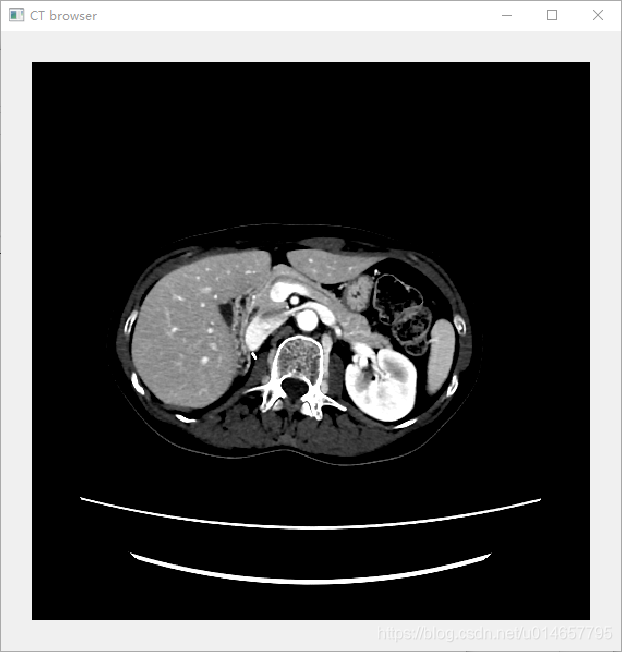

数据集原图为:

程序效果图为: